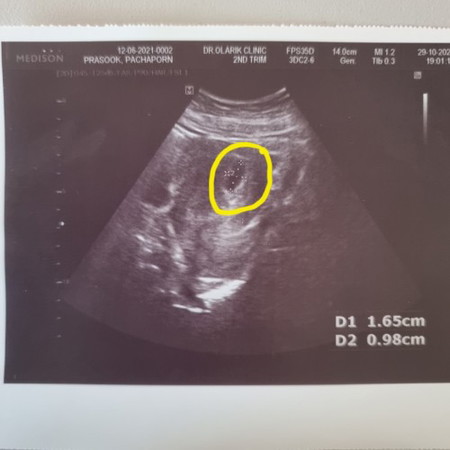

6 สัปดาห์เจอแต่ถุงการตั้งครรภ์ แต่ยังไม่เจอตัวน้องเลย แม่ๆท่านไหนเป็นเหมือนกันบ้างคะ ยังพอมีหวังไหมคะ 😭😭

มีแม่ที่เคยโพสต์เก่าๆ โพสต์ถามแบบนี้ หลายคนหมอบอกให้รอซาวด์อีกทีตอน 9-10 สัปดาห์ บางคนไม่เจอตอน 9 สัปดาห์ ก็รอ 12 สัปดาห์ค่ะ เพราะ 6 สัปดาห์ยังเล็กเกินกว่าจะสรุป และอายุครรภ์บางคนคลาดเคลื่อนกว่าที่เข้าใจตอนแรก เด็กอาจจะอายุน้อยกว่าที่เข้าใจ หรือมากกว่าก็ได้ค่ะ อย่าพึ่งวิตกเกินไป